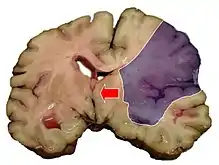

Midline shift is a shift of the brain past its center line.[1] The sign may be evident on neuroimaging such as CT scanning.[1] The sign is considered ominous because it is commonly associated with a distortion of the brain stem that can cause serious dysfunction evidenced by abnormal posturing and failure of the pupils to constrict in response to light.[1] Midline shift is often associated with high intracranial pressure (ICP), which can be deadly.[1] In fact, midline shift is a measure of ICP; presence of the former is an indication of the latter.[2] Presence of midline shift is an indication for neurosurgeons to take measures to monitor and control ICP.[1] Immediate surgery may be indicated when there is a midline shift of over 5 mm.[3][4] The sign can be caused by conditions including traumatic brain injury,[1] stroke, hematoma, or birth deformity that leads to a raised intracranial pressure.

Three main structures are commonly investigated when measuring midline shift. The most important of these is the septum pellucidum, which is a thin and linear layer of tissue located between the right and left ventricles.[7] It is easily found on CT or MRI images due to its unique hypodensity.[7] The other two important structures of the midline include the third ventricle and the pineal gland, which are both centrally located and caudal to the septum pellucidum.[6][7] Identifying the location of these structures on a damaged brain compared to an unaffected brain is another way of categorizing the severity of the midline shift. The terms mild, moderate, and severe are associated with the extent of increasing damage.